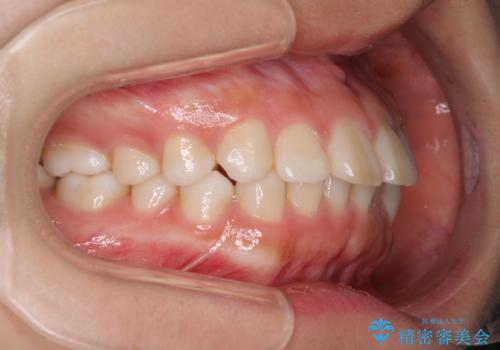

インビザラインによる軽度な出っ歯の矯正治療

- 上の前歯の出っ歯を治したいとのことで来院された患者様です。

上下顎ともにIPR(歯と歯の間を削る)と歯列全体の拡大によって口元が引っ込むように設計し、インビザラインにより治療を行うこととしました。

どこまで口元を引っ込めることができるのか、患者様自身も正直分からない部分があったため、少しずつ治療ゴールを変更しながら仕上げていきました。

気になっていた前歯の飛び出した印象は、最終的にはスッキリと引っ込み、大変満足していただきました。